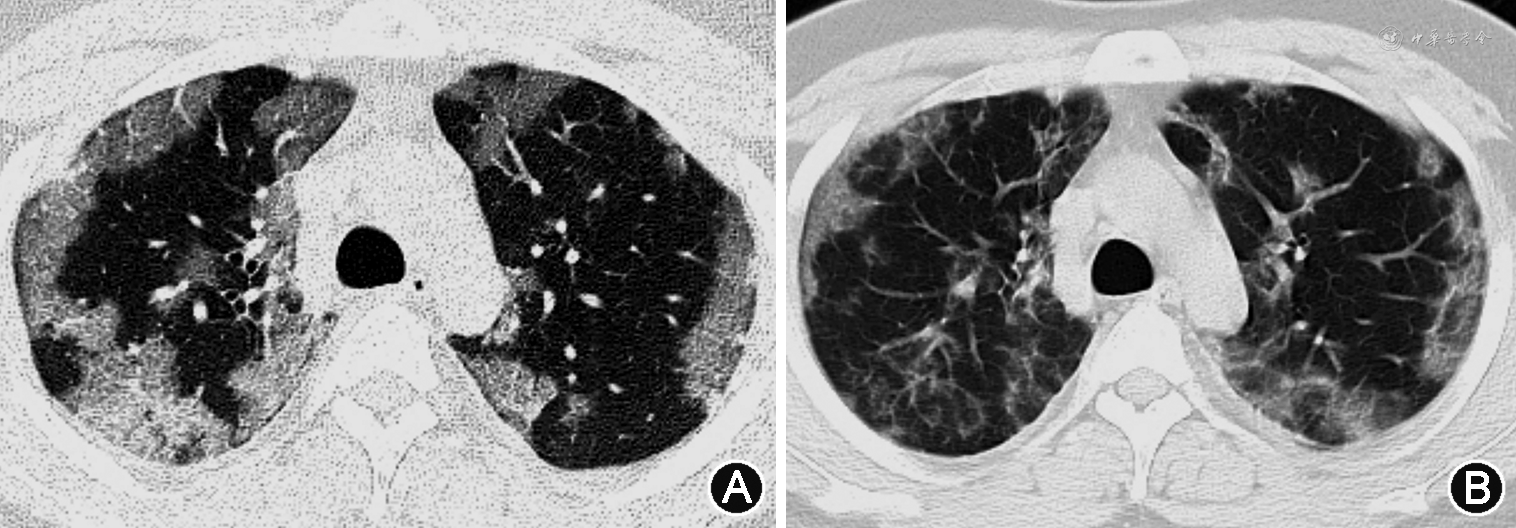

1. 重症病例:(1)X线:双肺受累多见,多发生在下肺[11, 12]。双肺纹理模糊,局限性或弥漫性分布的磨玻璃样改变及实变,部分可见弥漫性网状或结节状阴影。病程进展,病灶范围扩大,单侧病变可进展为双侧病变,单灶或多灶病变可进展为弥漫性病变,磨玻璃改变可融合为大片状实变[13]。可伴有胸腔积液[13]。合并肺气肿时,在病毒性肺炎基础上可见肺野透光度增强;合并细菌性肺炎时,表现为局灶性片状高密度影(图1)。(2)CT:单纯甲型H1N1流感重症肺炎病变常累及多个肺段及肺叶,病变可随机分布,但以双肺中下部周边为主[14, 15, 16, 17]。病变多表现为GGO和实变,或二者混合存在。磨玻璃阴影多位于周边,实变多靠近肺门,其内可见空气支气管征[18, 19, 20, 21](图1、2)。随病情进展,GGO会转化为实变,实变吸收也会转变成GGO。此外,还可见支气管血管束增粗、牵拉性支气管扩张等表现[16,22, 23](图3)。小叶间隔增厚、小叶中心结节等表现由于病情进展常常被掩盖,恢复期可见[24]。肺门及纵隔淋巴结肿大、胸腔积液和胸膜增厚等表现相对少见[25, 26]。肺栓塞亦可见,且发生风险较高[11,27]。可合并其他细菌性肺炎,进而形成合并性影像表现[12, 13,17]。治疗后恢复吸收阶段,病灶大多数可吸收,呈肺内广泛条索状、斑片状改变,甚至消失,部分病灶残留纤维瘢痕[22, 23]。

甲型H1N1流感重症肺炎进展快、吸收消散亦快。吸收往往从肺实变开始,表现为肺阴影变淡和密度不均,以及不同程度的纤维化改变[36](图5)。GGO及实变1周内出现,2周达到峰值,4周及以后吸收或消失[23]。纤维化在发病第1周即可出现,在发病第3周达到峰值,然后缓慢下降。对于病程较长的危重症患者,恢复吸收相对较慢[37](图5)。黎淑娟等[38]将甲型H1N1流感重症肺炎病变CT动态变化分成3种类型:先进展后吸收型、先吸收和进展并存后吸收型以及逐渐吸收型。